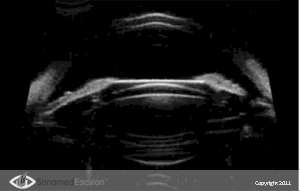

Ультразвуковой биомикроскоп VuMAX® включает в себя очень важную функцию пред- и послеоперационной диагностики при имплантации ИОЛ. Можно совершенно отчетливо увидеть и оценить такие факторы и параметры, как расстояние “sulcus-to-sulcus”, толщина хрусталика, анатомия борозды, форма и размеры цилиарного тела, а также другие анатомические характеристики. Данные параметры очень важны и полезны при выборе типа, дизайна и оптической силы ИОЛ.

При послеоперационной диагностике VuMAX® позволяет хирургу наглядно представить позицию ИОЛ и ее взаимодействие с различными структурами переднего отрезка. Появление имплантируемых контактных линз (?КЛ), ставшее очень хорошей альтернативой для некоторых пациентов, дает превосходные результаты при правильном их расположении. VuMAX® обеспечивает точные и правильные измерения “борозда – борозда” и/или “угол – угол” (в зависимости от типа имплантируемой ?КЛ).

При послеоперационной диагностике с помощью VuMAX® хирург может получить ряд очень важных данных, которые недоступны без использования высокочастотной ультразвуковой биомикроскопии. Совершенно четко на эхограмме можно проследить следующие параметры: правильно ли расположены опорные элементы линзы, расположена ли она по центру и нет ли контакта имплантированной линзы с нежелательными структурами.